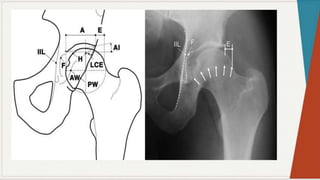

Radiografia Simples:

◗ Incidência ântero-posterior:

observar

as

características: espaços

articulares e

linhas

seguint

es

pélvica

s,

presença de qualquer doença óssea, ângulo colo-

diafisário, forma da cabeça femoral, presença de

osteófitos, evidência de fratura ou luxação,

evidência de deformação pélvica.